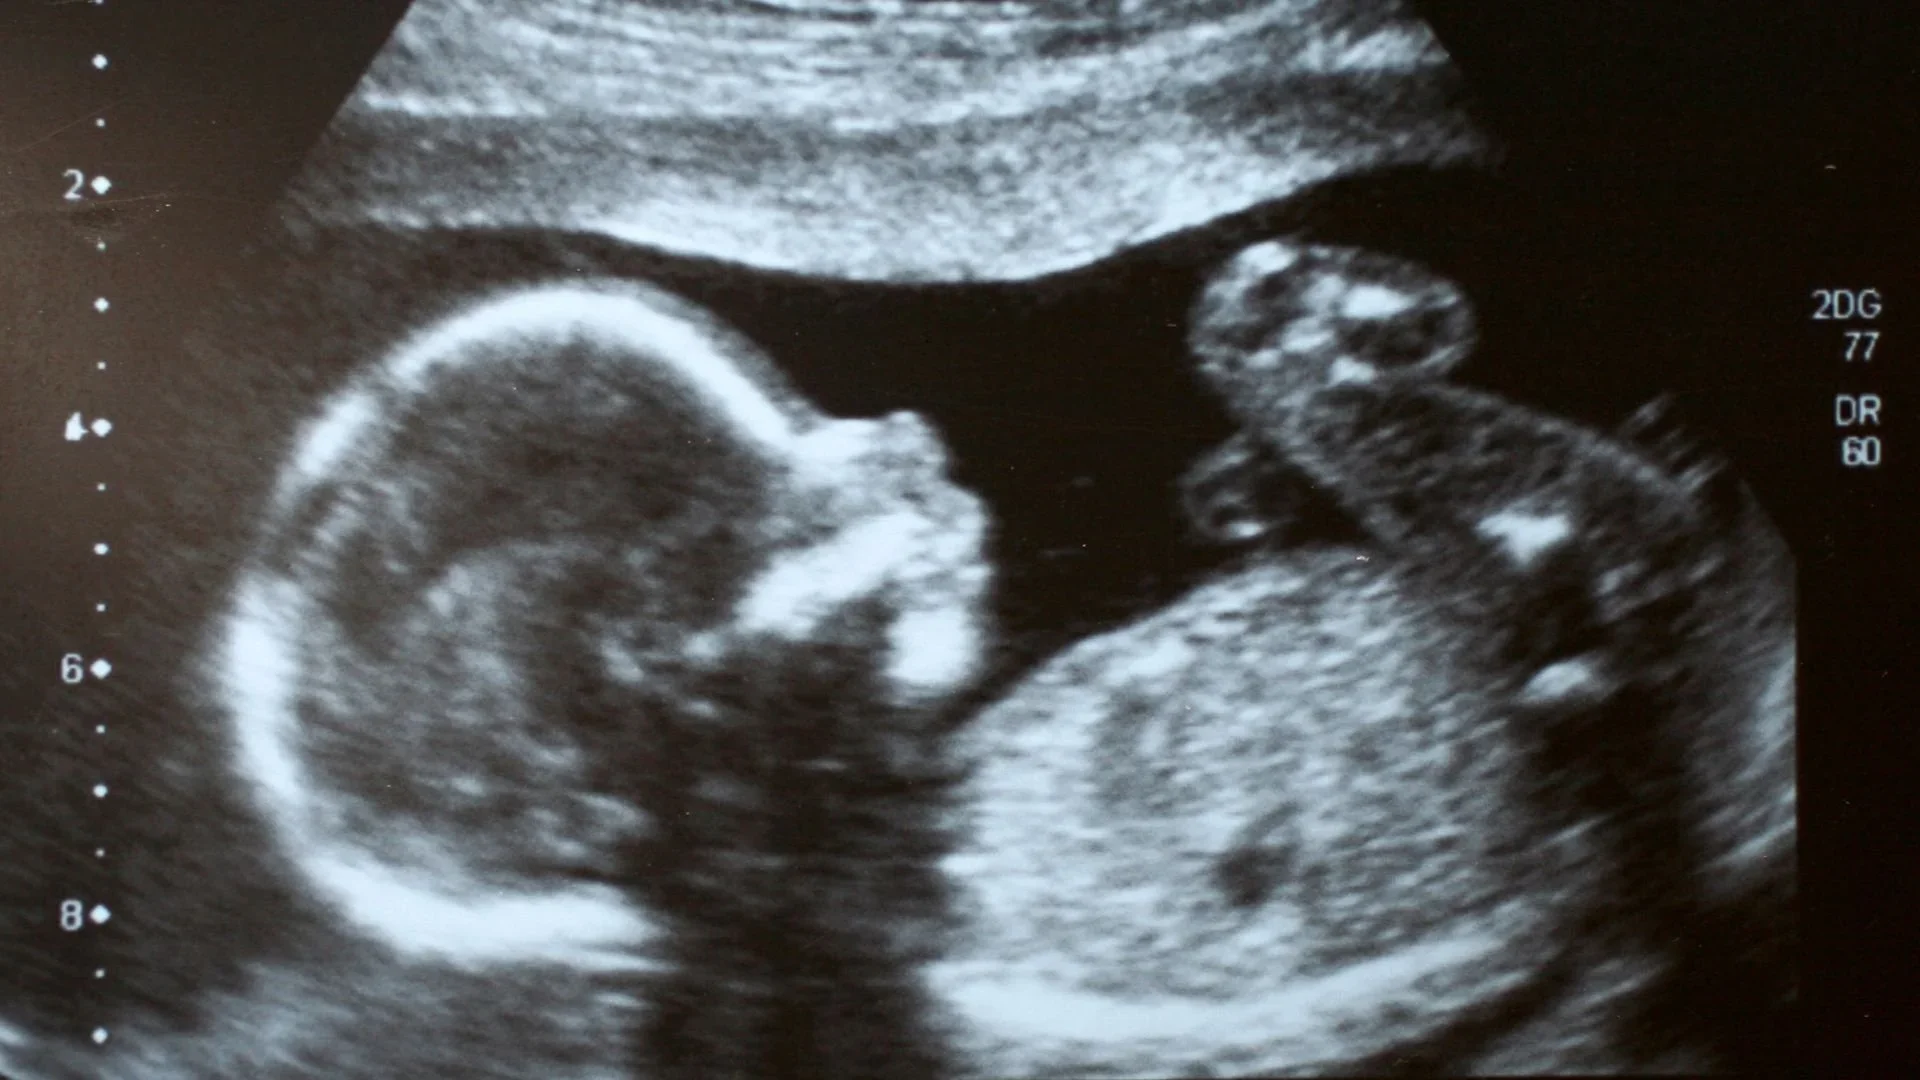

We understand how important it is to have support and resources when you need it the most. Diagnosis Day for your baby is the hardest day. We’d love to offer support for this crucial time of taking in what life for your unborn baby and life as a family will be like.

Below you will find a document of information for new parents that have just learned about a Spina Bifida diagnosis with resources and online support groups.